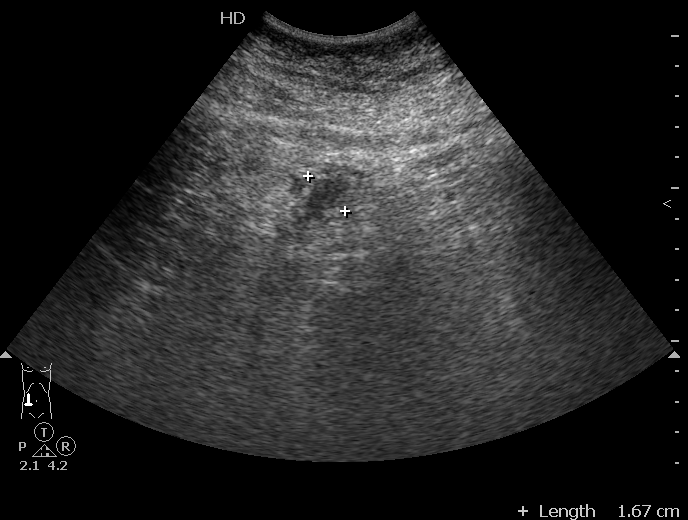

Парень с болями в правом мезогастриуме.